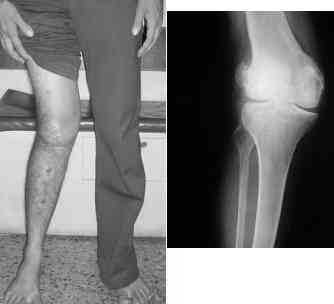

At present, he has a valgus deformity of the knee, with 0-45 degrees of movt. The knee is stable to examination, could not be corrected to neutral from the existing valgus, and despite the deformity he is walking on it, albeit with pain and some difficulty.

He was referred to me for correction of his deformity.

More images follow in subsequent mails.